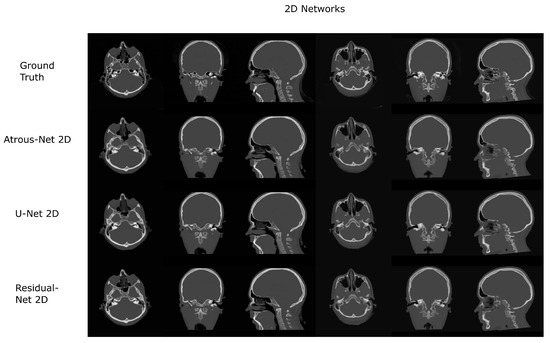

Figure 6. Head results using 2D networks.

3.1. Head Dataset Results

The results for all tissues using the head dataset are depicted in Table 1, Table 2 and Table 3; the results using only the bone voxels are detailed in Table 4, Table 5 and Table 6; the results using only the fat voxels are detailed in Table 7, Table 8 and Table 9; and the results using only the soft-tissue voxels are detailed in Table 10, Table 11 and Table 12. The best performing 2D network for the head dataset was the Residual-net. The results presented a MAE of 99.83 HU, a PSNR of 24.83 and a Pearson Coefficient of 0.931 in all tissues, and a MAE of 326.33 HU, a PSNR of 19.04 and a Pearson Coefficient of 0.826 in bone voxels. The ANOVA test revealed a statistically significant effect of the 2D architectures for MAE results (all tissues: F 2 , 36 = 91.1 , p < 0.001 ; bone: F 2 , 36 = 74.2 , p < 0.001 ) and PSNR results (all tissues: F 2 , 36 = 99.3, p < 0.001 ; bone: F 2 , 36 = 85.6, p < 0.001 ). A paired t-test was used to compare the Residual-net to the other networks reporting also statistically significant differences in the MAE and in the PSNR (Table 13). Using 2D convolutions, the Atrous-net and the U-net performed 5% and 18% worse than the residual-net, respectively. Moreover, the U-net network was clearly behind the other networks using 2D convolutions. Nevertheless, the U-net in 3D-16 obtained a MAE of 89.54 HU, a PSNR of 25.69 and a Pearson Coefficient of 0.943 in all tissues, and a MAE of 289.10 HU, a PSNR of 20.05 and a Pearson Coefficient of 0.861 in bone voxels, which were the best results for the head dataset. The ANOVA test also reported a statistically significant effect of the 3D networks for the MAE (all tissues: F 2 , 36 = 63.2 , p < 0.001 ; bone F 2 , 36 = 189.8 , p < 0.001 ) and the PSNR (all tissues: F 2 , 36 = 10.5 , p < 0.001 ; bone: F 2 , 36 = 83.1 , p < 0.001 ). The post hoc paired t-test that is depicted in Table 14 also reported statistically significant differences in the MAE and PSNR after comparing each architecture. Summarizing, the results using 3D convolutions from the U-net were 17% and 10% better than those of the Atrous-net and Residual-net, respectively. Visual result examples of head pseudo-CTs are depicted in Figure 6 and Figure 7. Table 15 shows the time needed to synthesize a whole head volume using the different architectures.